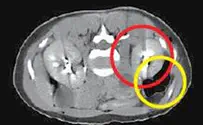

תוצאות בדיקות המעבדה הראו שבתום טיפולי הפריה של מטופלת הושג הריון, אך בבדיקת ההדמיה לא נראה עובר בחלל הרחם.